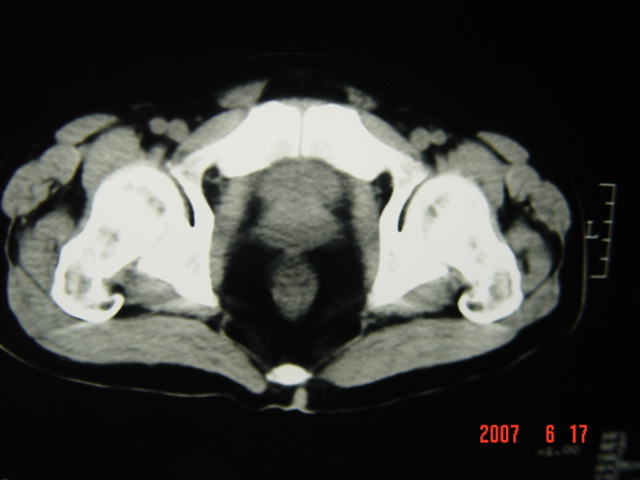

[br][br]以下是引用lkc8963在2007-6-17 13:32:00的发言:[br]完全支持邓主任意见:降/乙交界部占位性病变伴不全梗阻.做个增强或者be可能更好.